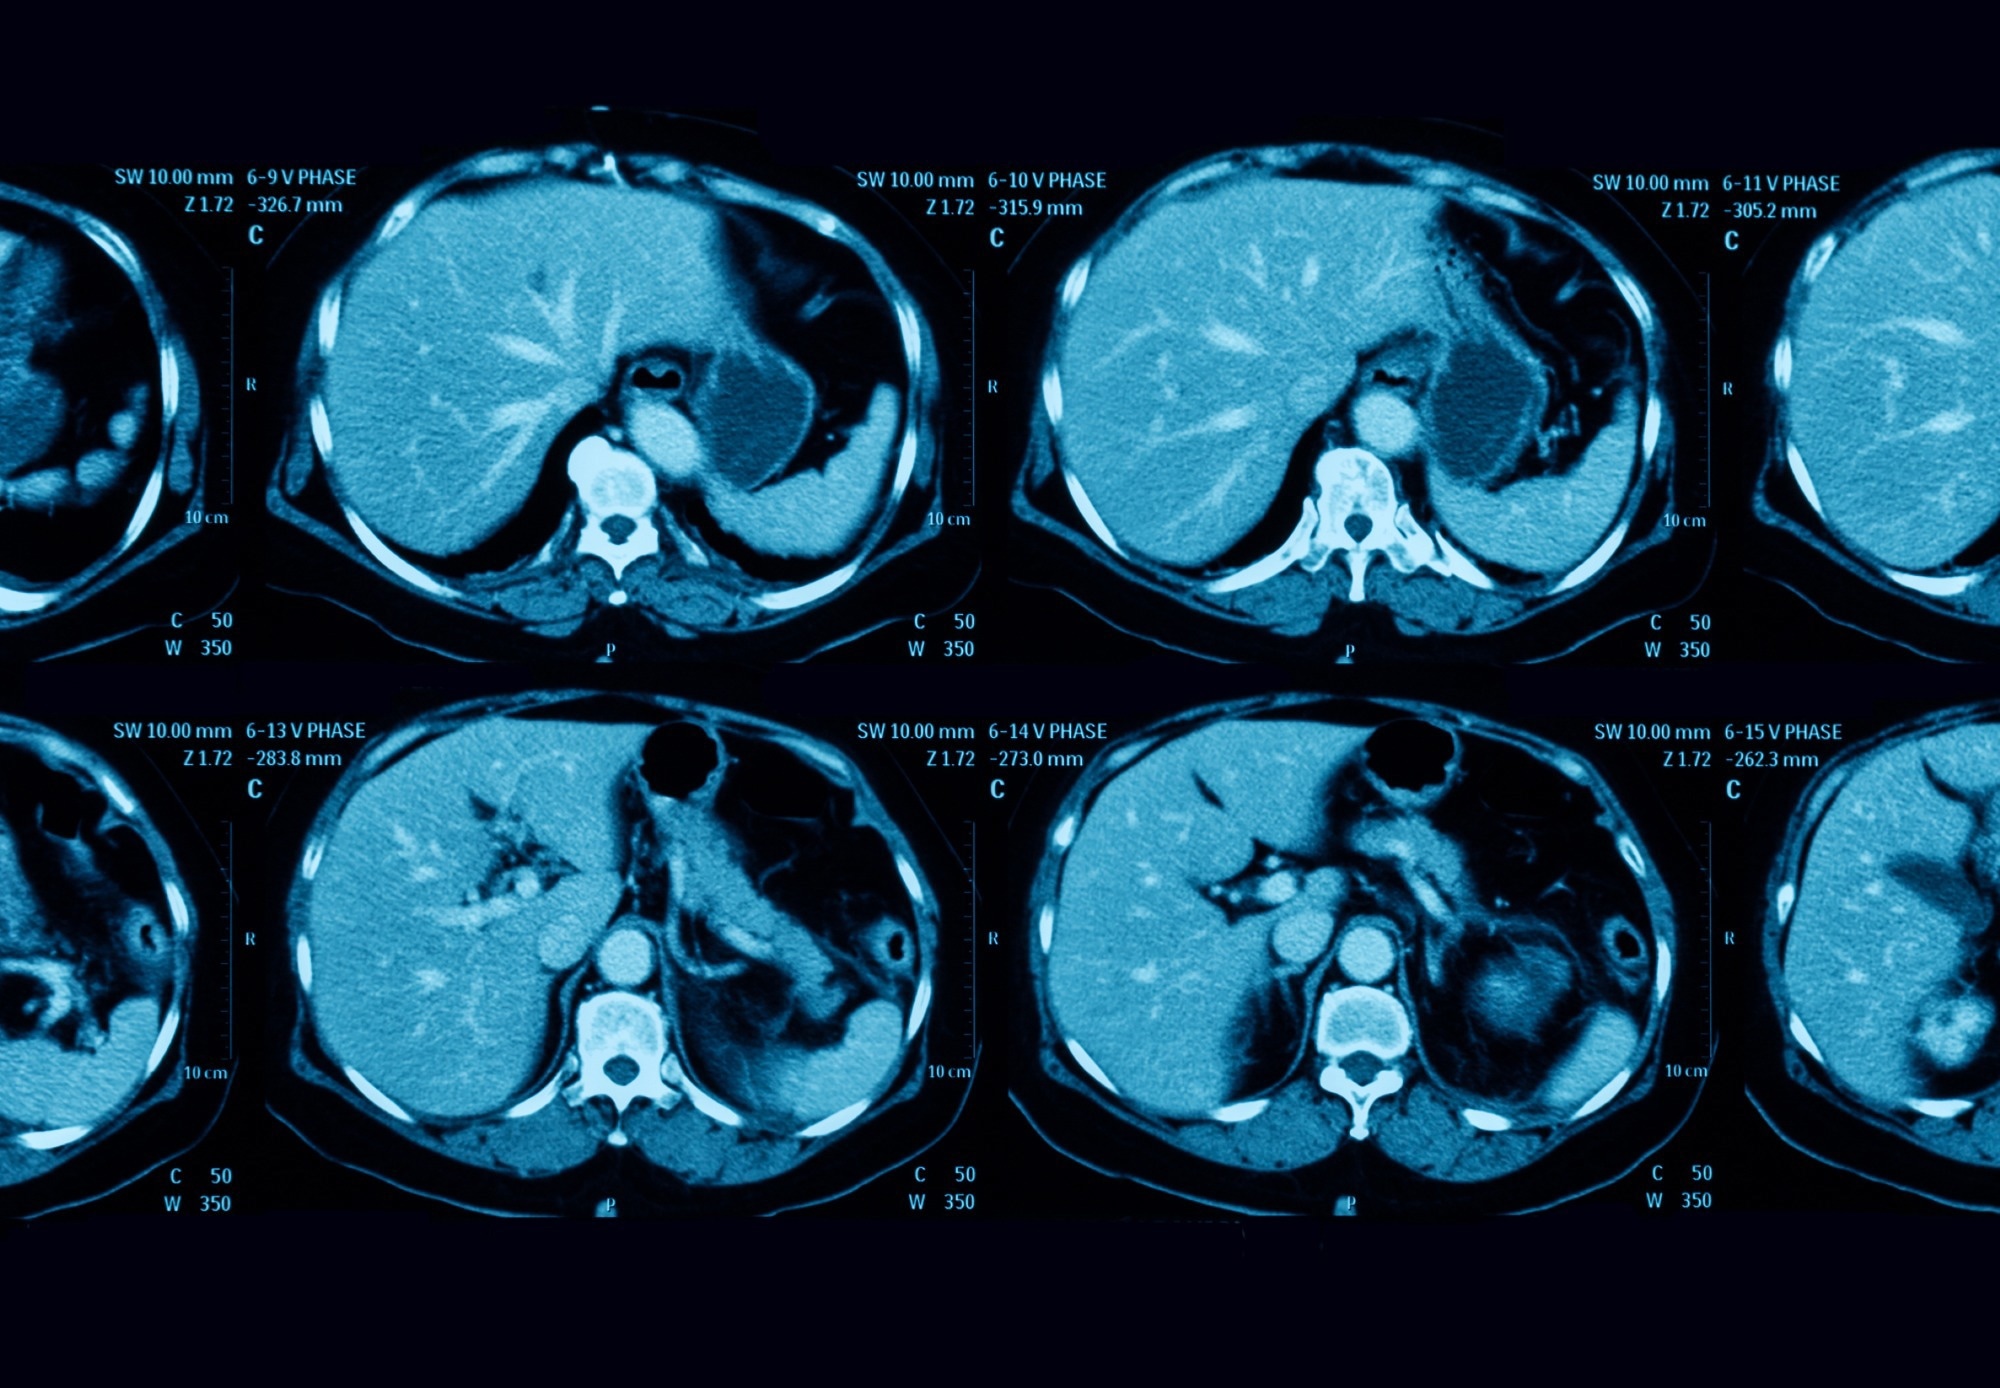

Study: Pancreatic Cancer Detection on CT Scans with Deep Learning: A Nationwide Population-based Study. Image Credit: Suttha Burawonk / ShutterstockStudy: Pancreatic Cancer Detection on CT Scans with Deep Learning: A Nationwide Population-based Study. Image Credit: Suttha Burawonk / Shutterstock

In a recent study published in the journal Radiology, researchers in Taiwan developed a deep learning (DL)–based computer-aided detection (CAD) tool to detect pancreatic cancer on contrast-enhanced abdominal computed tomography (CT) scans.

In the present study, researchers tested and validated a similar computer-aided detection (CAD) tool that harbored CNN for segmenting the pancreas on CT images. Additionally, this tool had an ensemble classifier with five independent classification CNNs to predict the presence of pancreatic cancer. They obtained all the CT scans analyzed in the portal venous phase, 70–80 seconds after intravenous administration of the contrast medium.